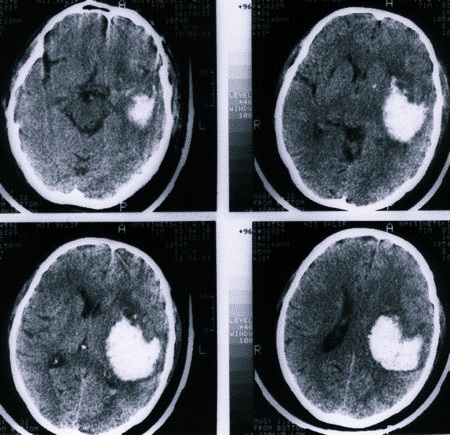

По скорости развития данной патологии принято отмечать несколько форм в соответствии с общепринятой классификацией:

- Острая. Симптомы неврологических нарушений появляются практически мгновенно, кровь прорывается в желудочки головного мозга, развивается обширный отек, сдавливающий мозговые структуры. Вероятность прерывания жизни пациента предельно высока.

- Подострая. Патологическое состояние так же развивается довольно быстро – в течение нескольких минут, но затем происходит стабилизация клинических признаков, отечность обычно не формируется сразу (спустя пару суток). Есть вероятность вторичного геморрагического инсульта, при котором состояние пациента будет хуже, чем при первичном. Прогноз зависит от ряда факторов, но при своевременном и правильном лечении он вполне приемлемый.

- Компьютерная томография.